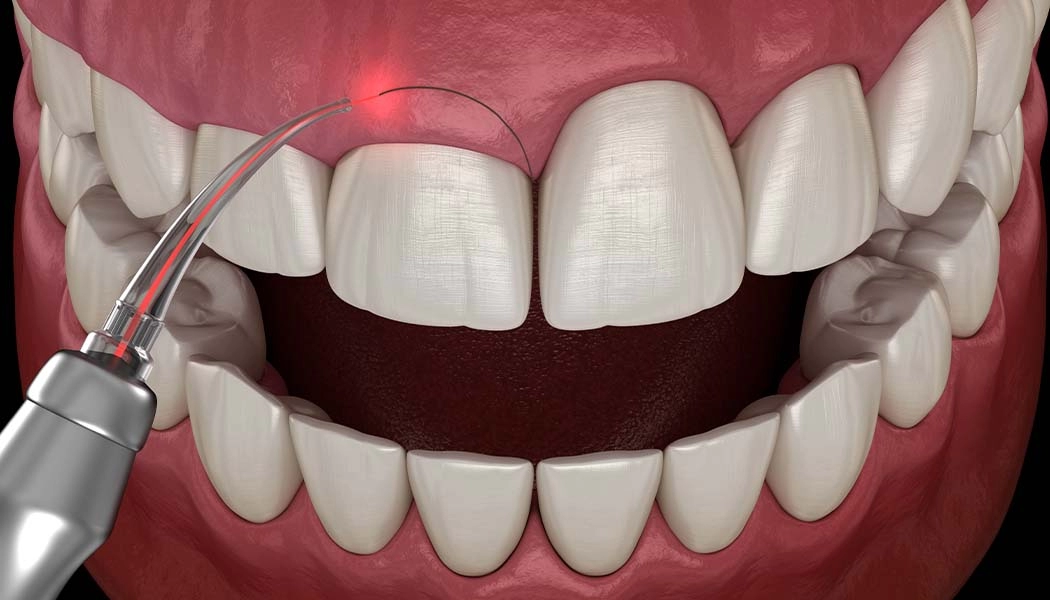

В терапевтической стоматологии лазер применяют при лечении стоматита, гингивита, герпеса, им обрабатывают пародонтальные карманы, а также используют при лечении кариеса. Для препарирования твердых тканей зуба используют, в основном, эрбиевый лазер; лазерный луч, попадая на ткани, испаряет их. Процедура практически безболезненная.